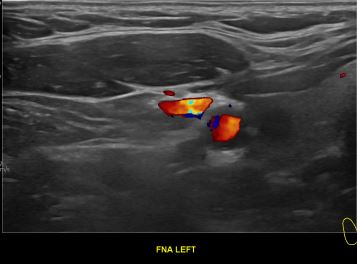

상기환자 외부건진 이상소견으로 내원하신 30대 중반 여성분으로

의심스러운 갑상선 좌엽 세포검사후 갑상선암으로 진단되었습니다